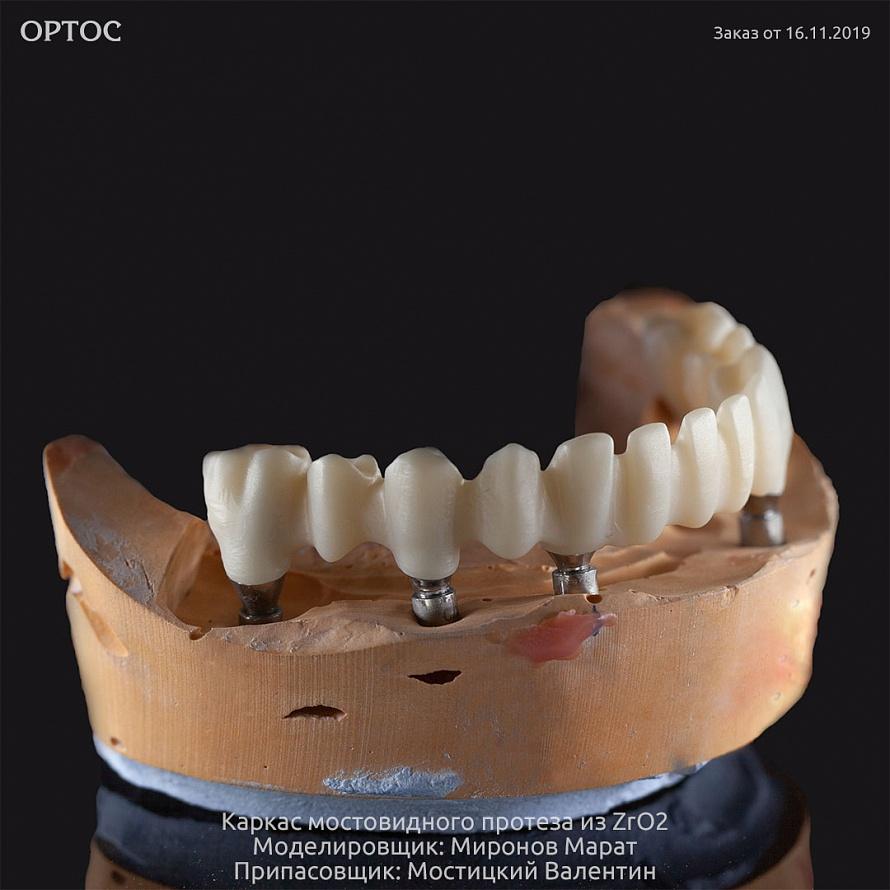

Зубные технологии: Все о циркониевых телескопических коронках

Раздел: Лаборатория идей